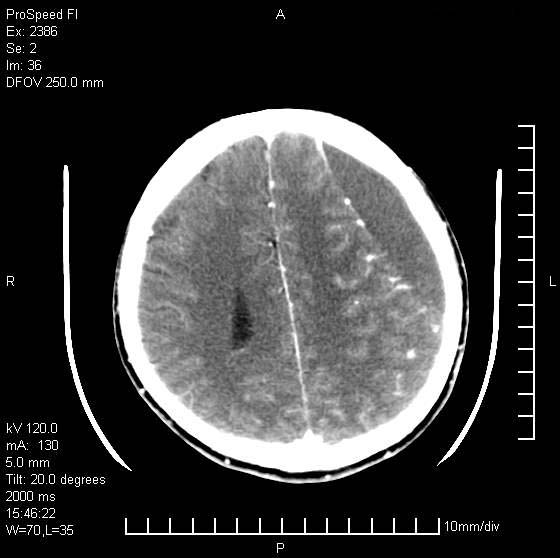

以下是引用天南地北在2007-9-19 18:43:00的发言:[br]典型慢性硬膜外血肿[br][br][本贴已被 天南地北 于 2007-9-19 18:44:11 修改过]

以下是引用曼一拍在2007-9-20 11:06:00的发言:[br]支持慢性硬膜下血肿.[br]慢性硬膜下积液:血肿有包膜,ct值稍高于脑脊液,增强可有染色。不典型者血肿可多呈梭形.是硬脑膜与蛛网膜之间的潜在腔隙内的血肿。[br]鉴别:[br]1\\硬膜外血肿:是颅脑外伤后脑膜或板障内血管破裂,血液在颅骨与硬膜之间积聚所致.通常是脑膜动脉破裂,也可因静脉窦破裂或颅骨的板障静脉出血,发生于外伤的着力部,常与颅骨骨折并存。脑膜动脉出血则急,若是板障静脉出血在则可有慢性。[br]2\\硬膜下积液:(硬膜下水瘤)[br]是由于蛛网膜破裂,脑脊液经蛛网膜破口进入硬膜下腔不能回流。或水肿阻塞而形成。[br]ct表现:颅骨内板下方新月形低密度区近似脑脊液密度;占位效应清,周围无脑水肿。[br]